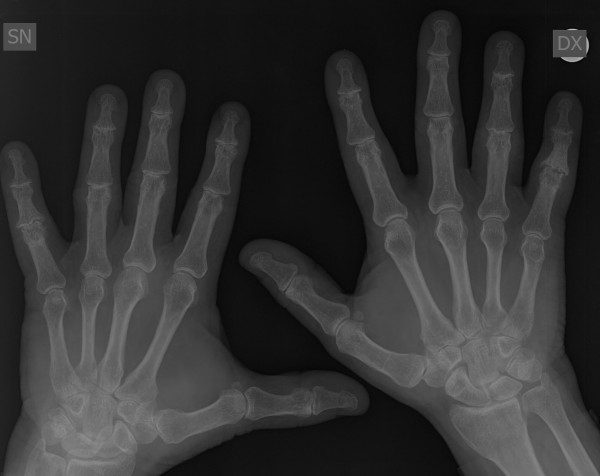

Mi piacerebbe avere un ulteriore parere sulla radiografia alle mani che allego anche per una eventuale cura da seguire. Grazie!!

0006B312.jpg

[ 24.9 KiB | Osservato 1617 volte ]

0006B311.jpg

[ 27.61 KiB | Osservato 1617 volte ]

0006B310.jpg

[ 32.51 KiB | Osservato 1617 volte ]

Non ha senso un parere del reumatologo quando esiste un referto del radiologo. Il problema potrebbe nascere se il quadro clinico e/o di laboratorio fossero in disaccordo con i dati radiologici. E' solo dal confronto dei 3 elementi (clinico in primis, poi radiologico e di laboratorio) che si può azzardare una diagnosi e quindi impostare un trattamento. Le macchine finora non sostituiscono del tutto il medico.